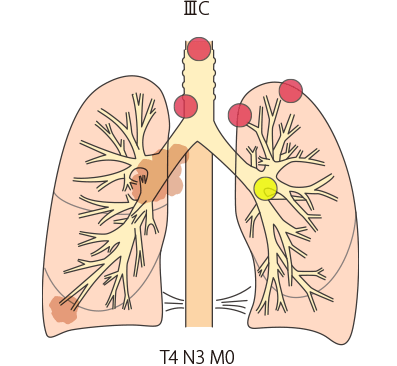

進行度の分類には、TNM分類が用いられ、T-原発腫瘍の進展度、N-リンパ節転移、M-遠隔転移の組み合わせによりステージが定められます。

肺がんのステージには、Ⅰ期(ⅠA、ⅠB)、Ⅱ期(ⅡA、ⅡB)、Ⅲ期(ⅢA、ⅢB、ⅢC)、Ⅳ期(ⅣA、ⅣB)があります。たとえば、肺のがんが小さく、肺の中だけにとどまっている場合はステージⅠ期に分類されます。がんの進行の程度に応じて、Ⅱ期、Ⅲ期、Ⅳ期とステージが上がっていきます(ステージ分類の詳細はこちら)。

| IIIC期 | T3、T4 | N3 | M0 |

IIIB・IIIC期(ステージ3):局所進行がん

IIIB期

IIIC期

TNM分類でⅢB・ⅢC期と分類された肺がんは、ⅢA期よりさらに進行した状態の局所進行がんとされています。原発巣側の肺外にリンパ節転移が生じています(N2またはN3)。手術ですべてを取り切ることは難しく、手術をしてもがんが残ってしまう可能性が高いことから、基本的に手術はおこないません。

標準的な治療法としては、化学療法、放射線治療の併用が行われます。その後、免疫チェックポイント阻害薬による免疫療法が行われることもあります。

小細胞肺がんでは化学療法と放射線治療の併用が検討されます。

| IIIC期 | T3、T4 | N3 | M0 |

IIIB・IIIC期(ステージ3):局所進行がん

IIIB期

IIIC期

TNM分類でⅢB・ⅢC期と分類された肺がんは、ⅢA期よりさらに進行した状態の局所進行がんとされています。原発巣側の肺外にリンパ節転移が生じています(N2またはN3)。手術ですべてを取り切ることは難しく、手術をしてもがんが残ってしまう可能性が高いことから、基本的に手術はおこないません。

標準的な治療法としては、化学療法、放射線治療の併用が行われます。その後、免疫チェックポイント阻害薬による免疫療法が行われることもあります。

小細胞肺がんでは化学療法と放射線治療の併用が検討されます。